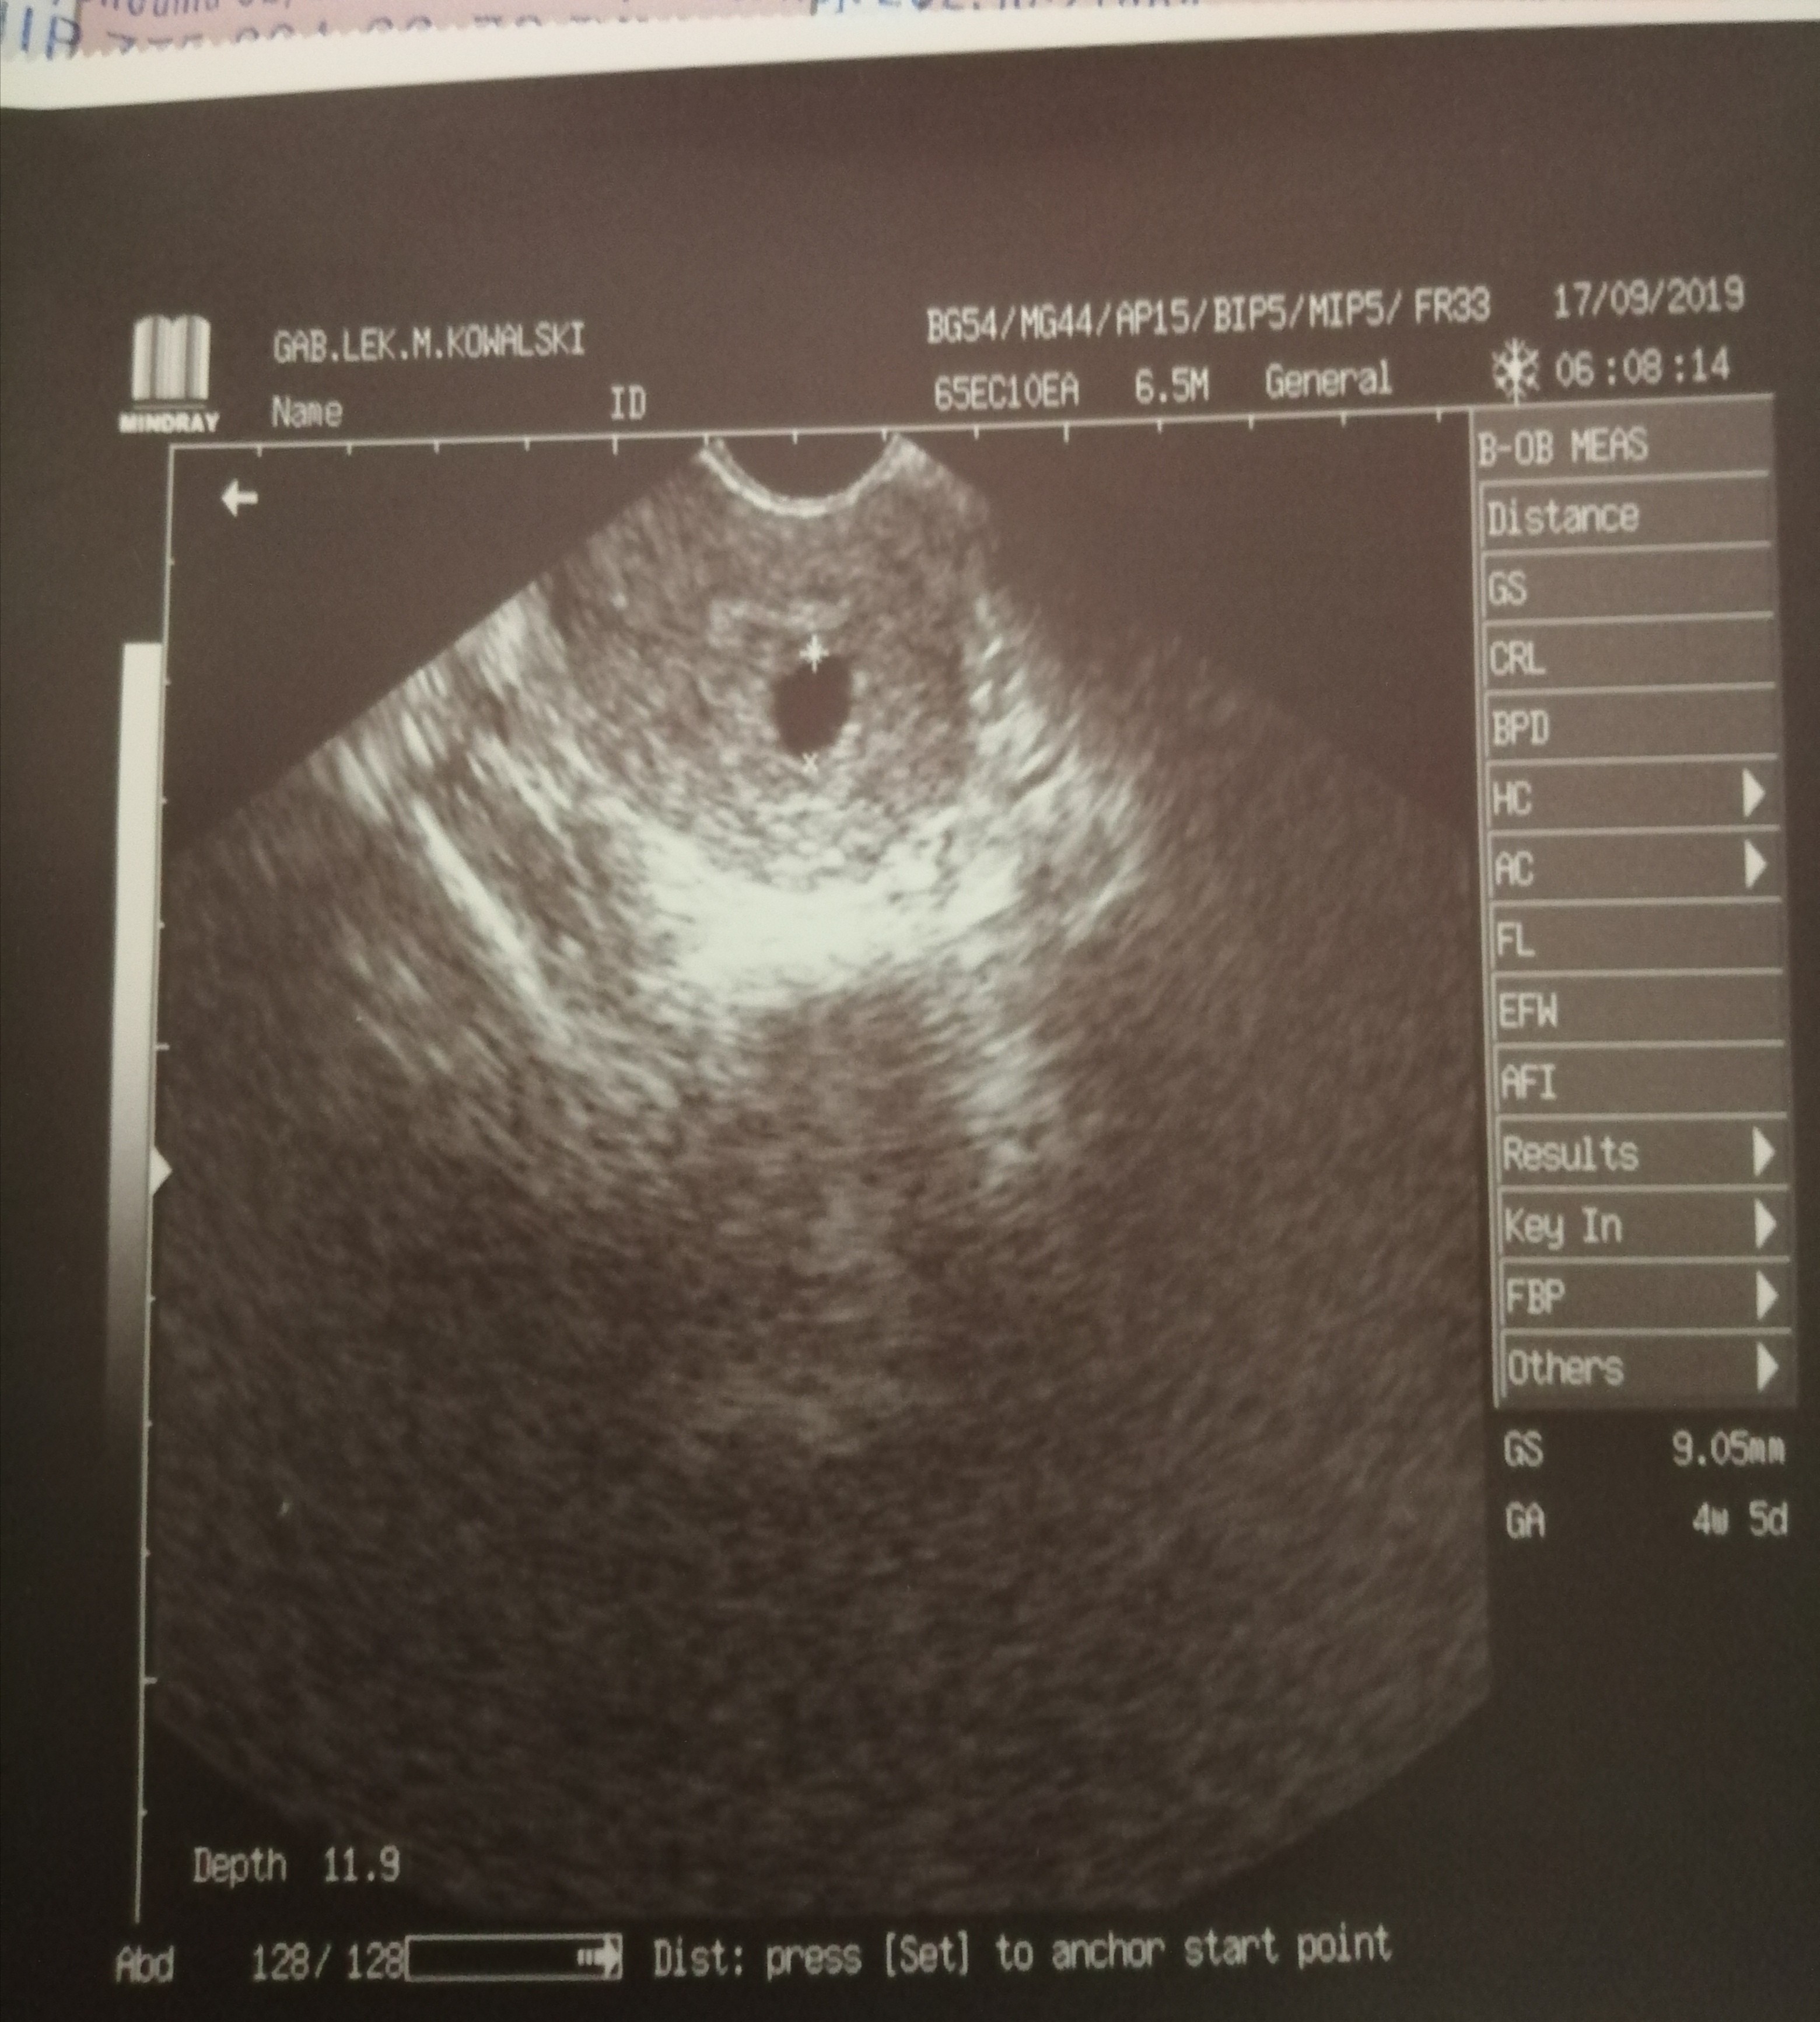

17 poszłam do gina, który potraktował mnie w sposób wręcz mechaniczny, dosłownie usg trwało moment, po chwili stwierdził, że jest tylko pęcherzyk ciążowy, a czy coś z tego będzie... Może się utrzyma, może poleci. Teraz wkrecałam sobie, że może jest pusty pęcherzyk ciążowy. W piątek poszłam zrobić bete i dzisiaj powtórzyłam. Nie mam pojęcia czy jest to prawidłowy przyrost, a do wizyty oczywiście u innego ginekologa, chyba zwariuje.

20.09 usg widoczny pęcherzyk 13mm z ciałkiem żółtym 3mm bez zarodka. I określił wiek ciąży na 6t 1d. Echa serca nie uwidoczniono.

Nastepnego dnia zrobiłam beta hcg - 47435,50. Beta z dziś - 68884,30